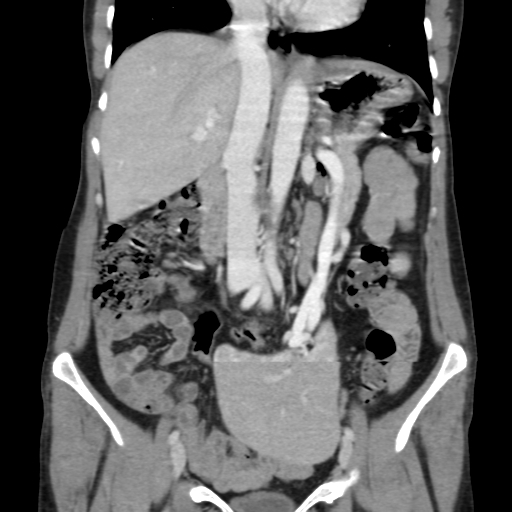

CT of the abdomen demonstrates a mass arising from the greater curvature of the body of the stomach. It is centrally ulcerated with locules of gas and contrast seen within it, but without evidence of perforation. It is a focal abnormality with thick heaped-up shoulders.

At the splenic hilum there appears to be an enlarged lymph node (this should be confirmed on thin slice and coronal reformats). No convincing evidence of metastatic disease.

The left kidney is atrophic and contains a number of what appear to be hyperdense cysts (which should be confirmed on ultrasound). The right kidney has a large simple cyst.

This patient went on to have a total gastrectomy after the stomach tumour was identified on gastroscopy.